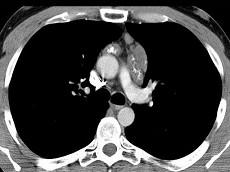

问题 21岁,女,颈部淋巴结肿大,无压痛,请结合CT检查选出最可能的诊断 ( )

选项 A、转移性淋巴结肿大 B、间皮囊肿 C、淋巴结核 D、结节病 E、淋巴瘤

答案 E